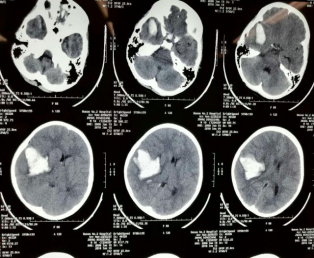

●高血压性脑出血微创穿刺引流术

高血压性脑出血是高血压病最严重的并发症之一,常发生于50~70岁,男性略多,冬春季易发。高血压病常导致脑底的小动脉发生病理性变化,突出的表现是在这些小动脉的管壁上发生玻璃样或纤维样变性和局灶性出血、缺血和坏死,削弱了血管壁的强度,出现局限性的扩张,并可形成微小动脉瘤。因情绪激动、过度脑力与体力劳动或其他因素引起血压剧烈升高,导致已病变的脑血管破裂出血所致。

适应证:高血压性脑出血,尤其是长期使用阿司匹林、氯吡格雷抗血小板聚集或抗凝等药物,不适合开颅手术患者。

优点:术前只需头颅CT或MRI定位,穿刺准确,创伤小,恢复快,费用低。